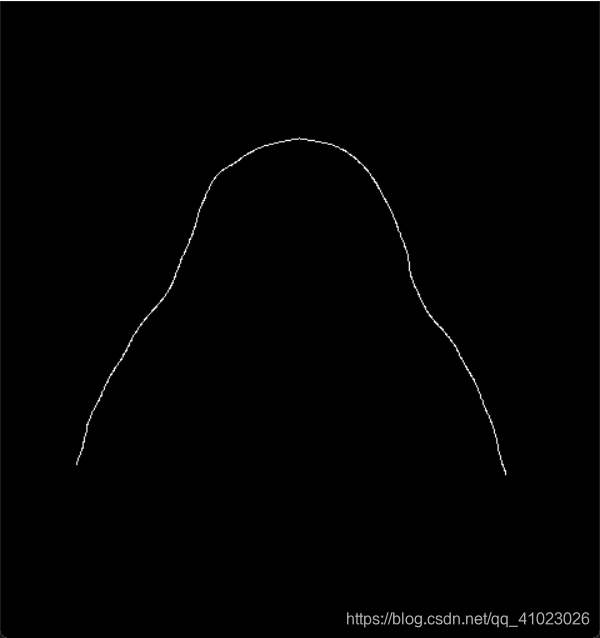

Mat srcMat6(srcMat5.size(), CV_8UC1);

ximgproc::thinning(srcMat5, srcMat6, ximgproc::THINNING_ZHANGSUEN);